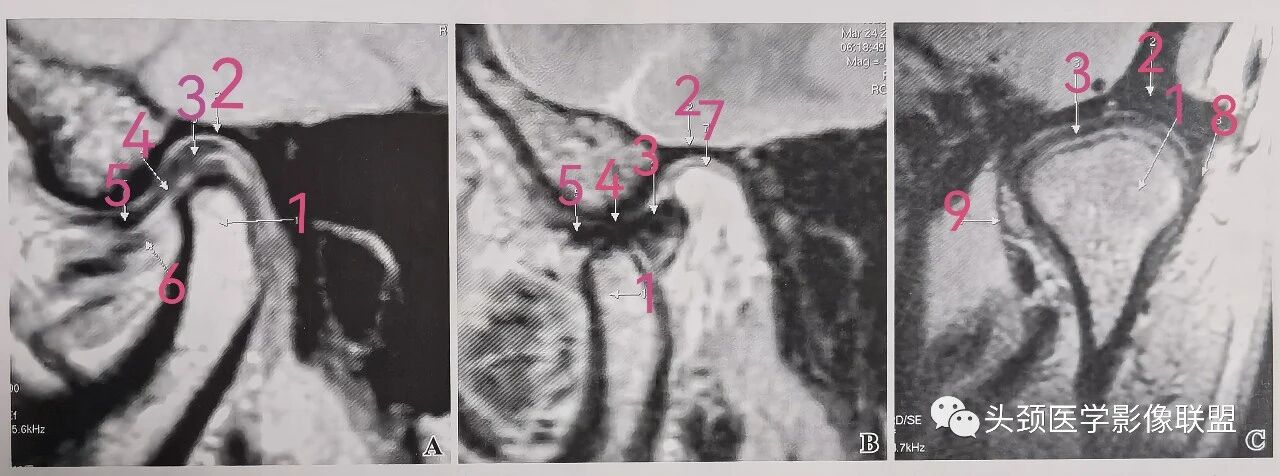

正常颞下颌关节 MRI

A. 矢状面闭口PD像,B.矢状面开口PD像,C.冠状面闭口PD像:1.下颌髁突;2.颞骨关节面(关节窝);3.关节盘后带;4.关节盘中带;5.关节盘前带;6.翼外肌上头和下头之间的纤维带;7.关节盘后附着;8.外侧关节囊;9.内侧关节囊。

闭口矢状面MRI上,下颌髁突位于颞骨关节窝内。与上述正常解剖描述相一致,关节盘后带覆盖于下颌髁突横嵴顶部,约相当于11-12点方位;关节盘中间带则与下颌髁突前斜面和颞骨关节结节后斜面相对应(图A)。关节盘中间带对应于髁突嵴顶的情况相对少见。开口后,随着下颌髁突和关节盘的向前运动,盘-髁关系也随之发生变化。开口矢状面MRI上,可见关节盘后带位于下颌髁突的后方,并与下颌髁突的后斜面相对应(图B)。下颌髁突顶部所对应的关节盘区域为其中间带或前带。下颌髁突通常向前运动于颞骨关节结节的下方或前下方。

冠状面MRI上,关节盘呈新月形。关节盘的内侧附着于髁突内侧下方和关节囊的内侧部分;关节盘的外侧附着于髁突外侧下方和关节囊的外侧部分。正常情况下,关节囊的内侧和外侧部分均可显示。关节囊一般不会向外膨隆。闭口位上,可见下颌髁突顶部有关节盘后带位于其上方(图C)。